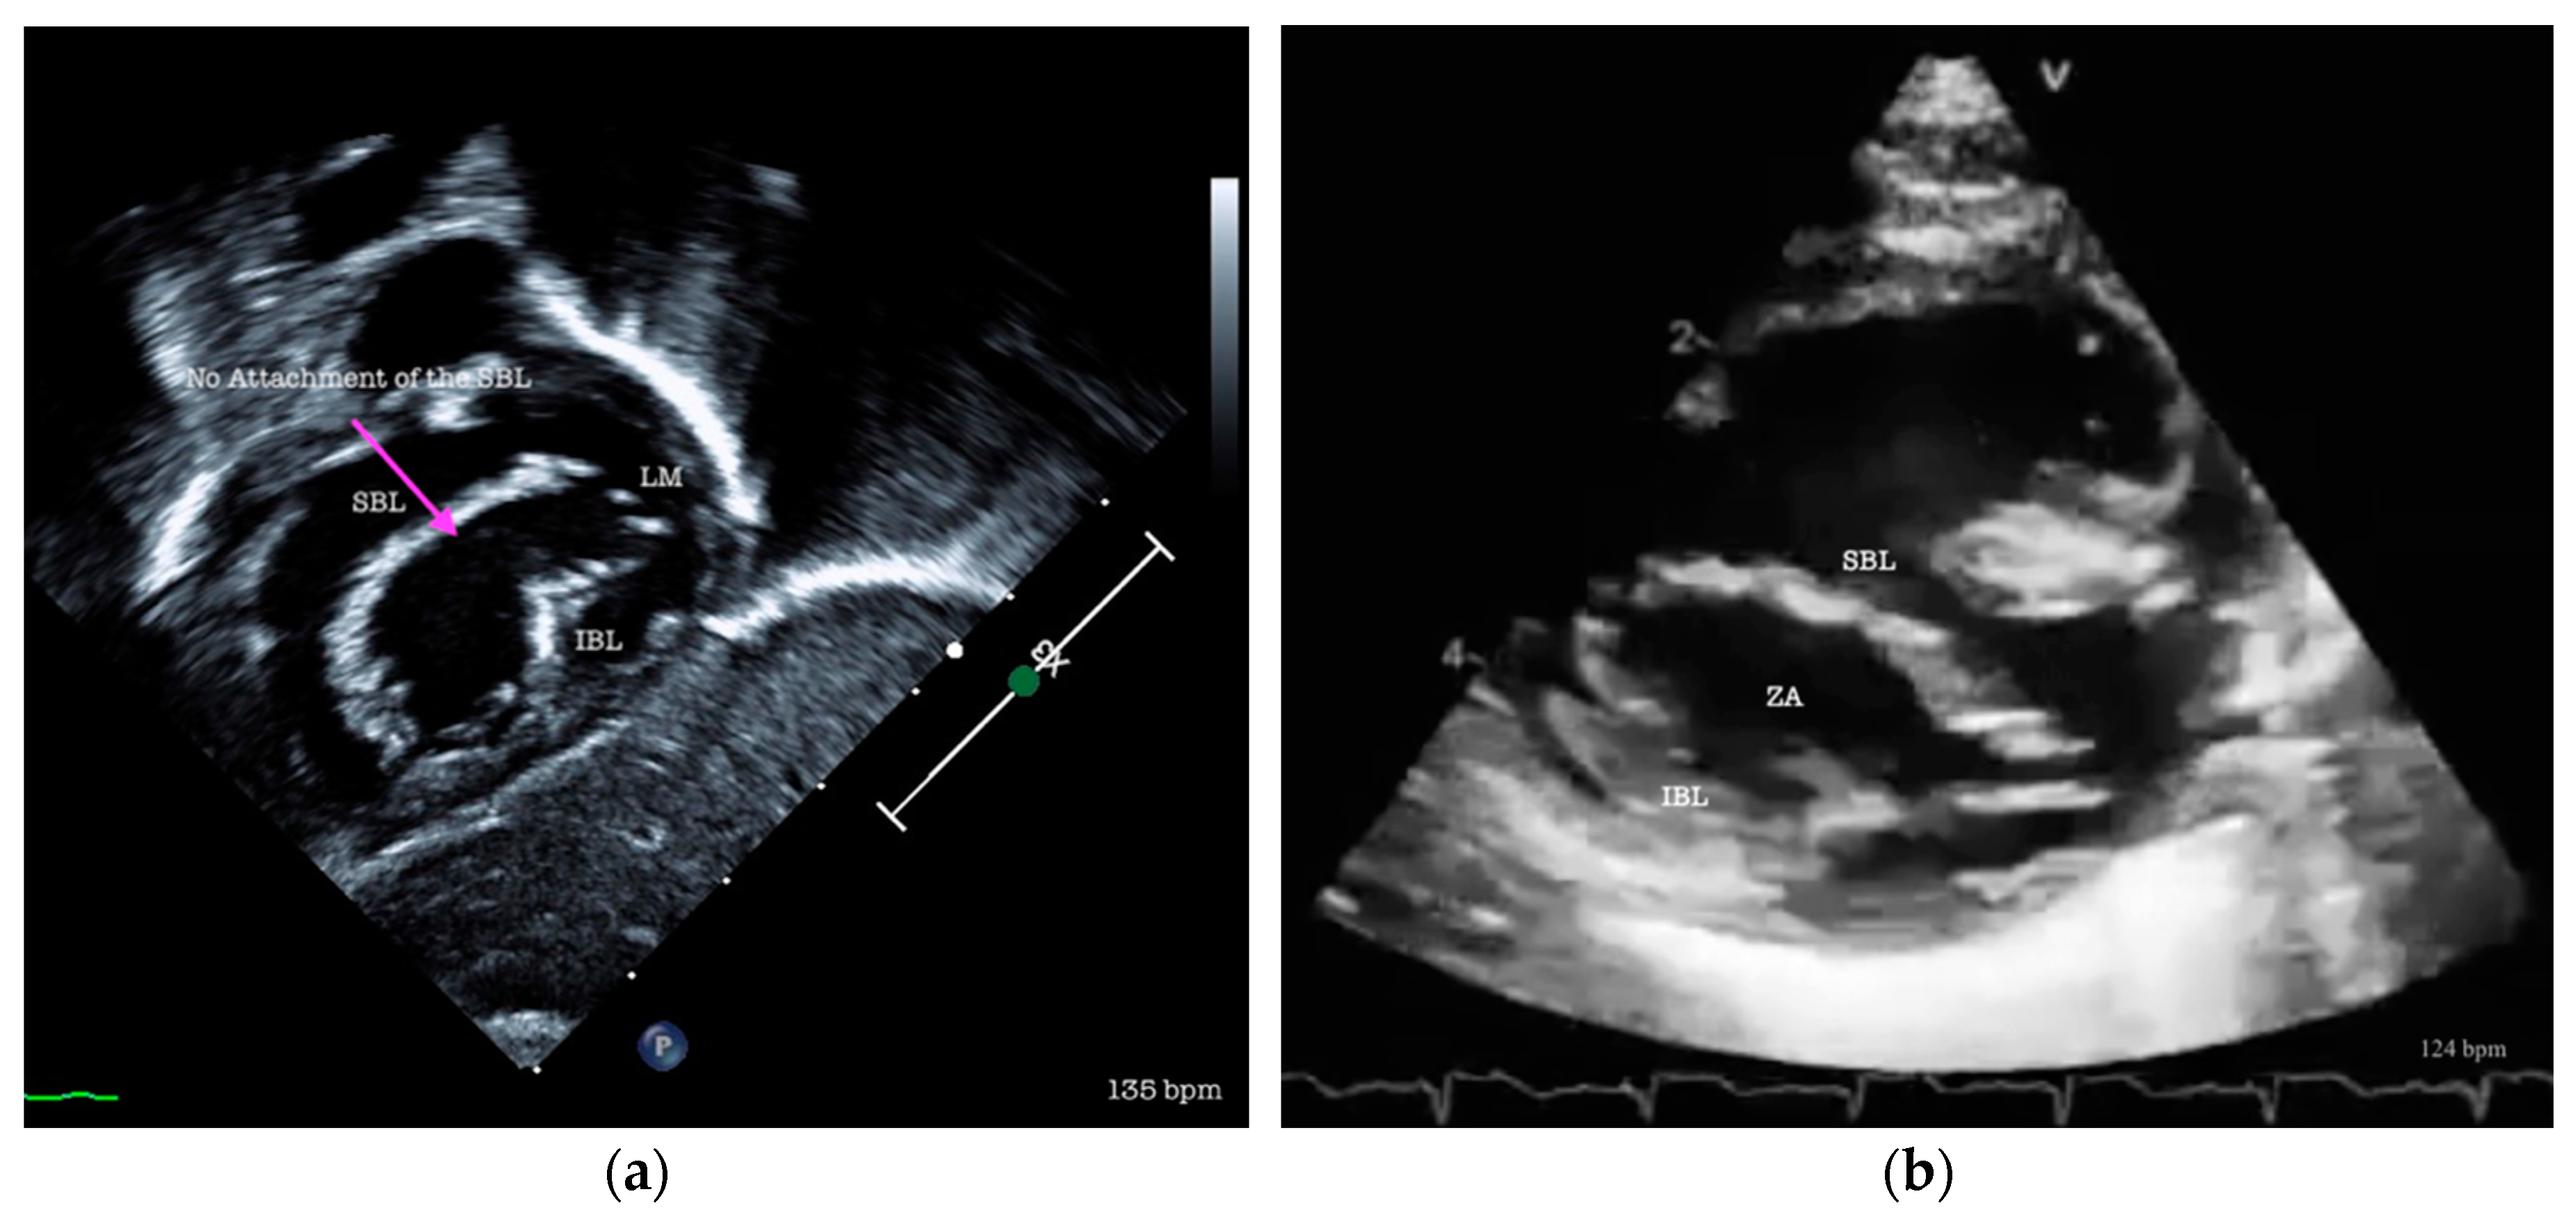

Figure 3. Ventricular septal defect Rastelli TYPE C – no superior leaflet bridging attachment. (a) subcostal view in transthoracic echocardiography showing common atrio-ventricular valve with 5 leaflets and no attachment of the superior bridging leaflet (Atrioventricular septal defect Rastelli type C). SBL, superior bridging leaflet; LM, left mural leaflet; IBL, inferior bridging leaflet; (b) modified parasternal short axis showing a complete atrio-ventricular septal defect with no attachment of the superior bridging leaflet. SBL, superior bridging leaflet; ZA, zone of apposition; IBL, inferior bridging leaflet.